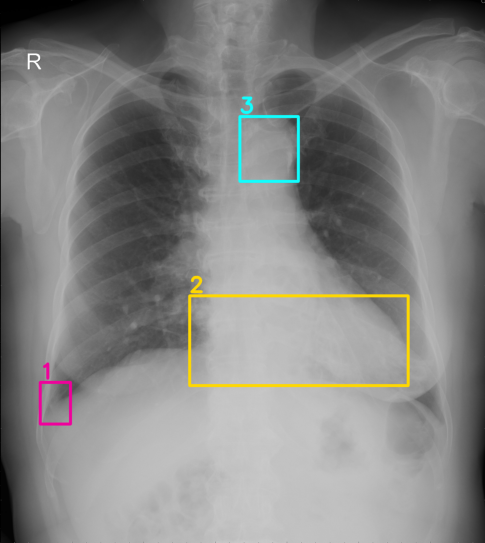

We firstly estimate the true labels using Weighted Boxes Fusion (WBF) algorithm [13]. This technique is used for combining predictions from multiple sources, i.e., using ensemble to achieve better prediction results or combining labels of different expert annotators. We describe the WBF algorithm in more detail in Algorithm 1. The final examples used to train deep learning detectors contain merged boxes with confidence scores. The visualization of fused boxes and the corresponding confidence scores are shown in Figure 2. Our fusion box algorithm emphasizes that the greater agreement between bounding boxes (e.g., two or three annotators have the same diagnosis for an abnormal finding on the image), the more likely the box annotation is correct.

Refer to caption

(a) The original annotations provided by multiple radiology experts. The same abnormal finding is represented by the sample color.

(b) Fused boxes with corresponding confidence scores after applied the WBF algorithm.

Figure 2: (a) Visualization of multiple expert annotations on a chest X-ray example from the VinDr-CXR dataset [5] and (b) the fused boxes with confidence scores obtained by the WBF algorithm.